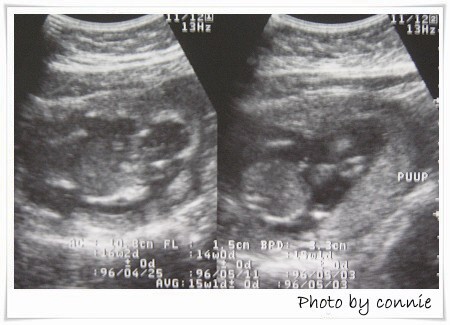

第三次產檢:

日期:95年11月11日

週數:15周+

血壓:116/91

體重:-1kg